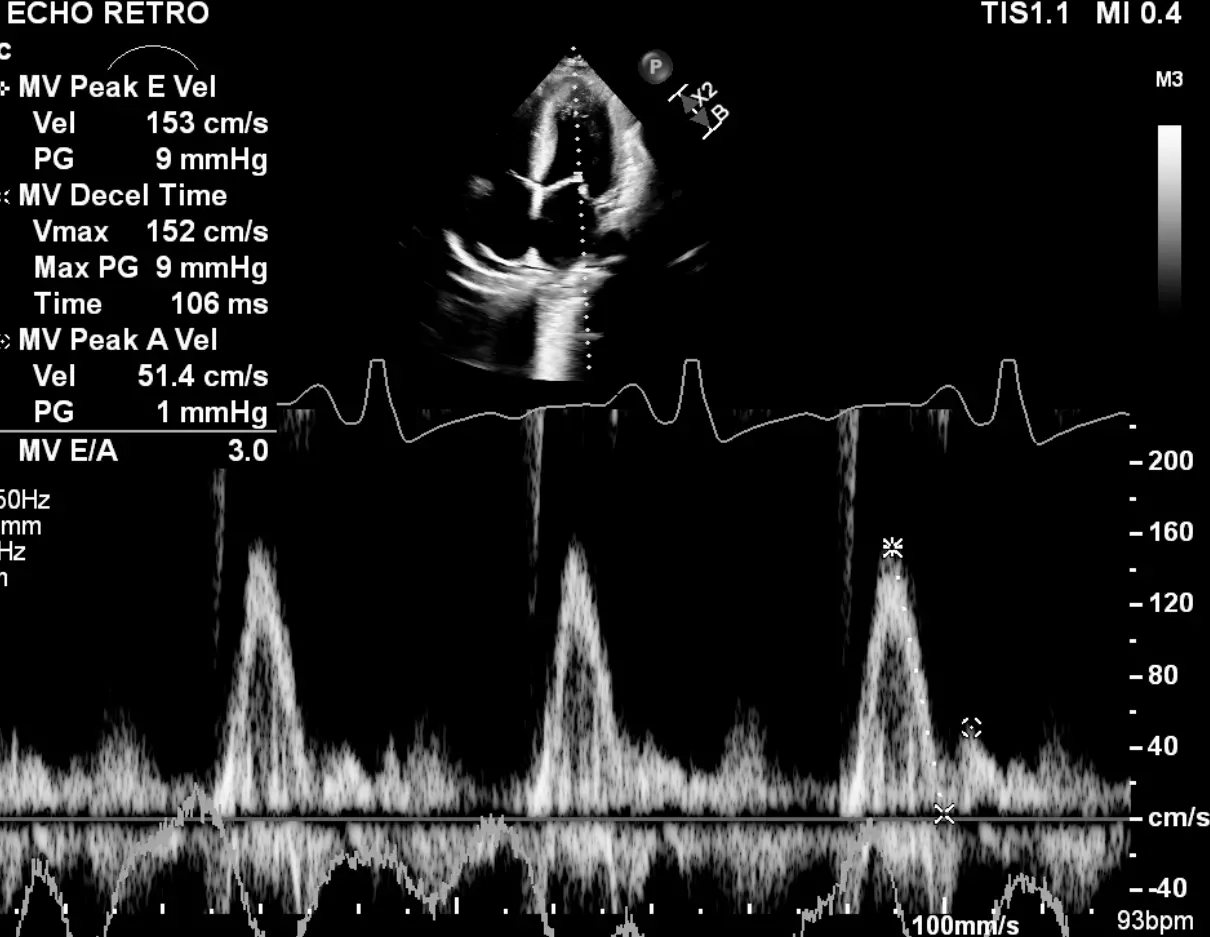

Example 1: Don’t Simply Binarize Based on Annular e’ Velocities

Mitral inflow pattern in a ~30 yo patient with severe LVH who initially presented with HTN emergency.

If you just base it off the patient having medial e’ >6, lateral e’ >7, or average >6.5, then you may conclude that she has normal diastolic function. However, I’d argue that this would be incorrect. The patient is a ~30 yo with severe LVH. Bearing in mind her young age, you should expect her e’ velocities to be much higher if she truly had normal diastology. With her very high E/A ratio, she has Grade 3 DD.